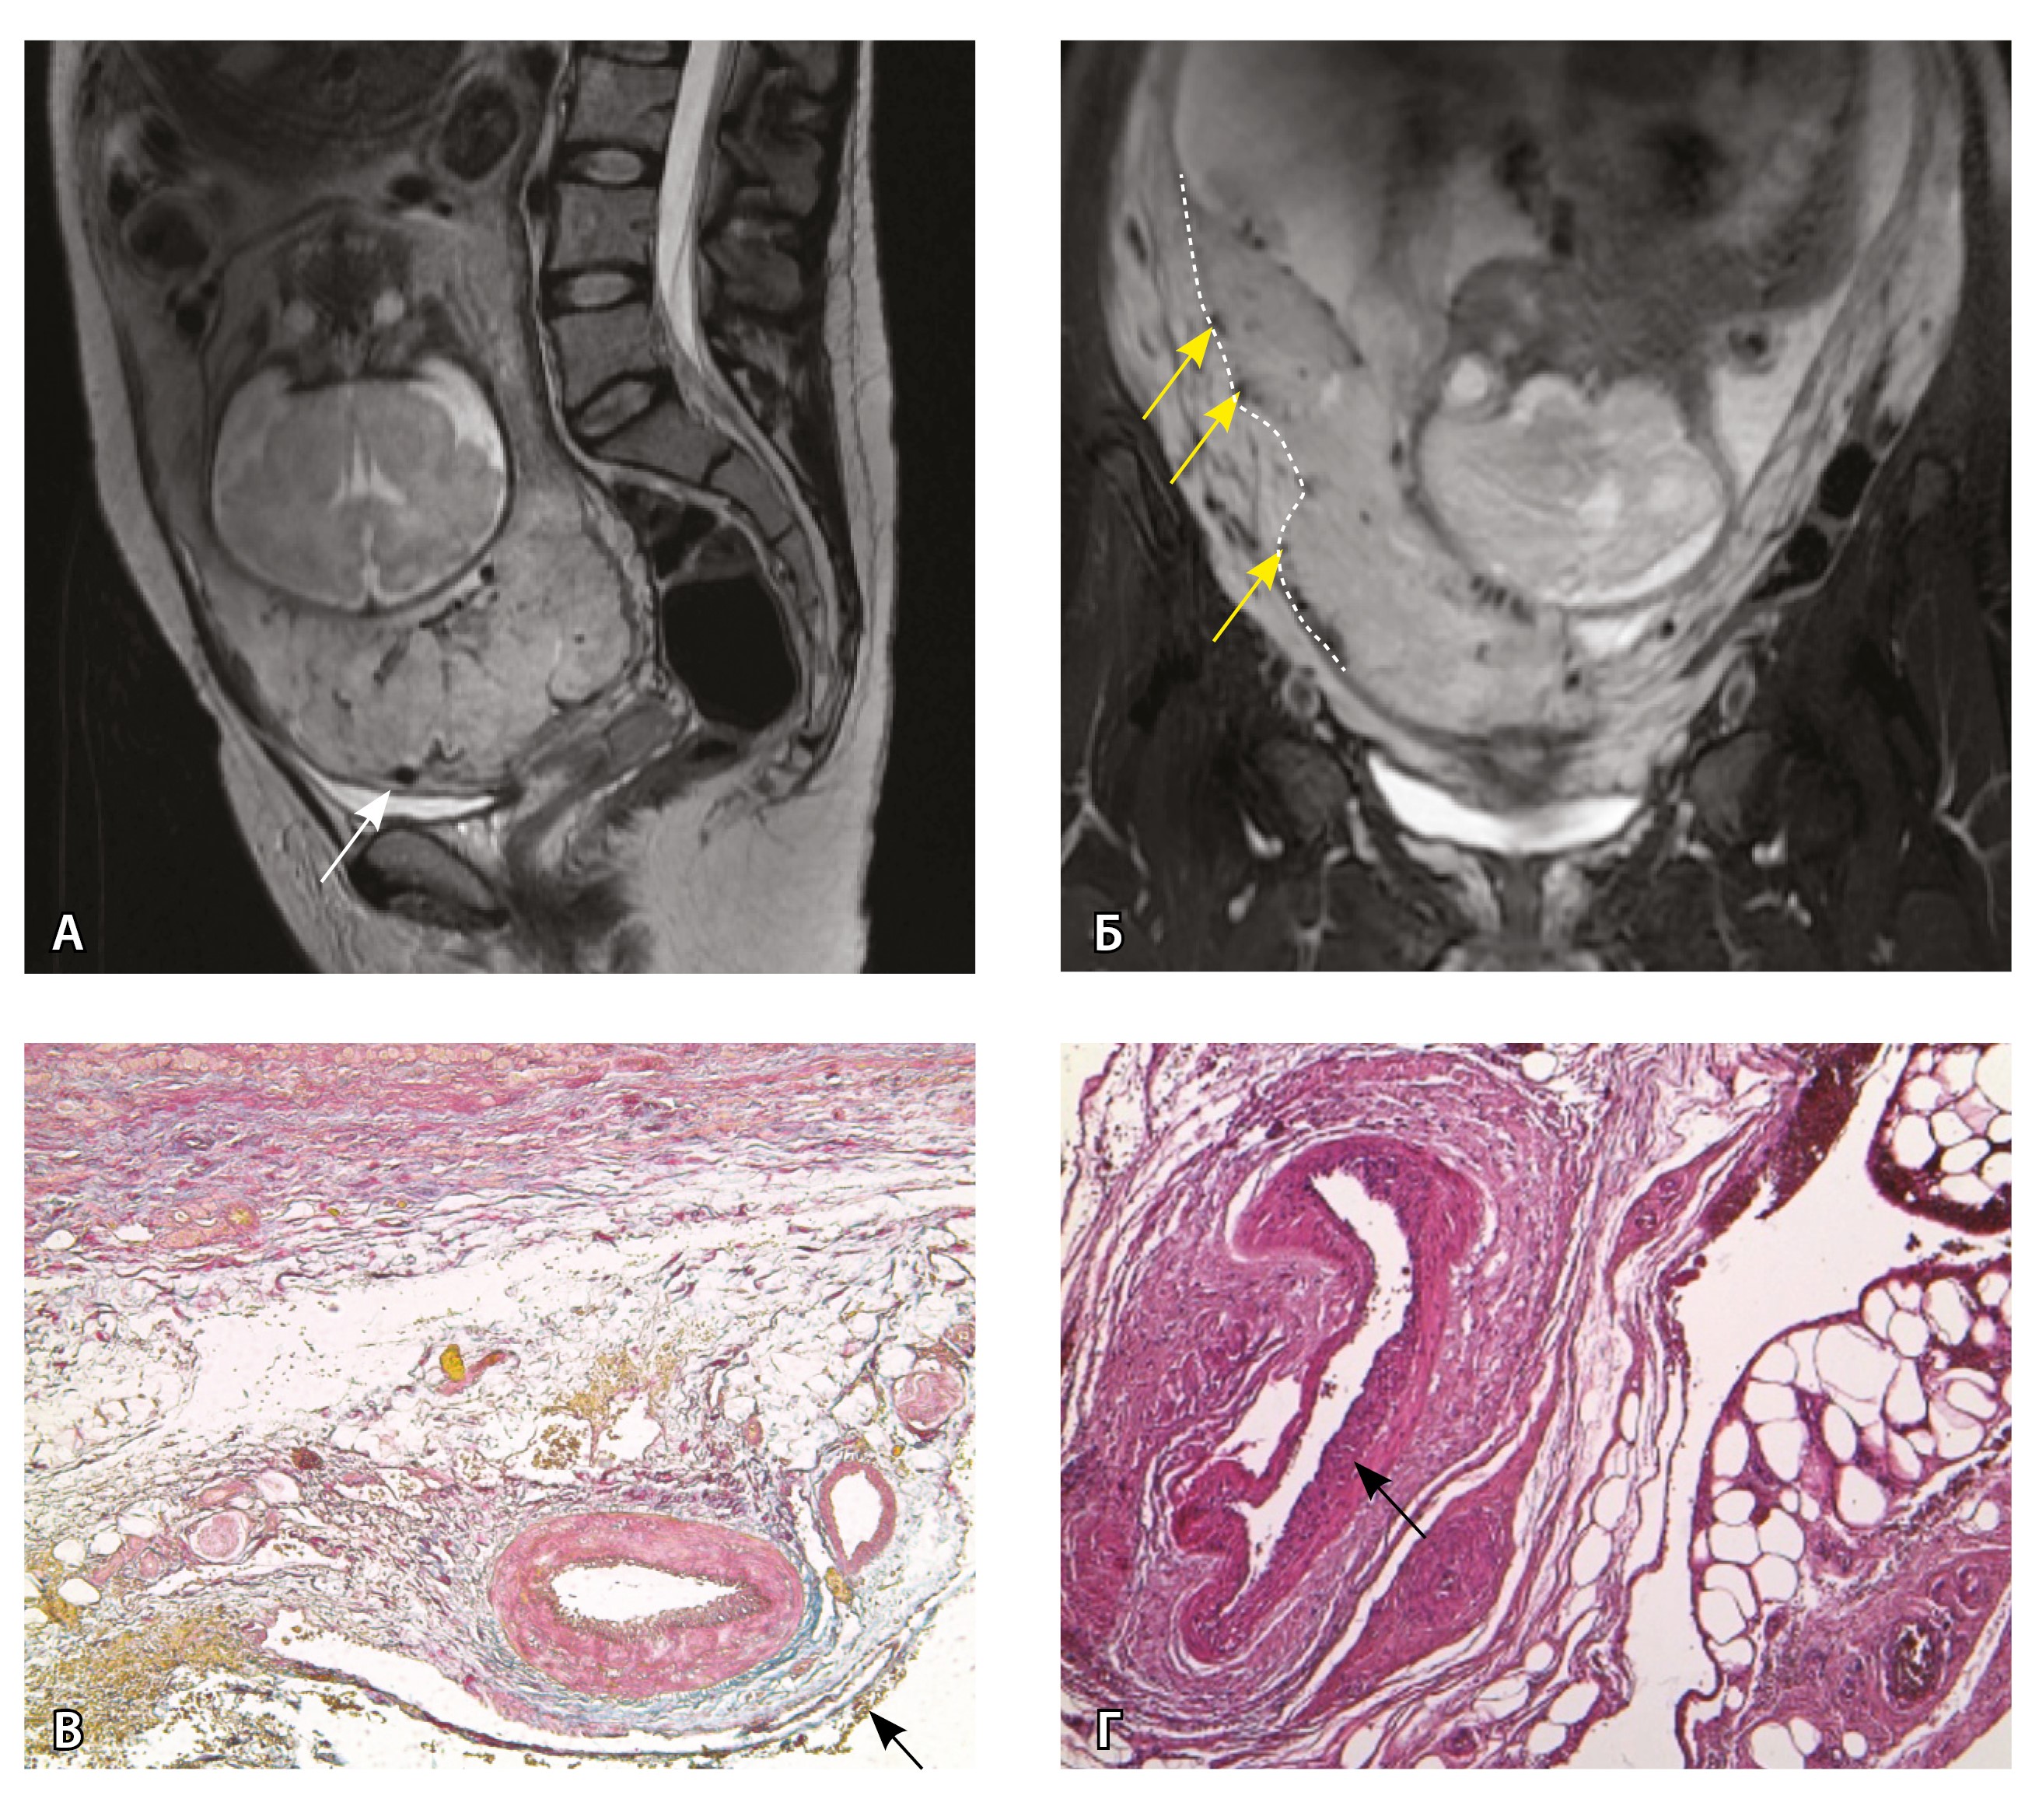

Сосуды 5-го типа. Наличие гиперваскуляризации за пределами матки по данным МРТ, на границе с мочевым пузырем с вовлечением его стенки, сосуды в области перешейка матки, параметрия, в том числе в сочетании с признаками фиброза, наличием рубцово-спаечных изменений и др. Можно предположить, что сосуды 5-го типа являются аналогом pl. рercreta PAS 3b, 3c (рис. 15).

Рис. 15. Беременность 34 недели, pl. percreta, PAS 3b по FIGO (A, Б), PAS 3c по FIGO (В). На магнитно-резонансных томограммах в режиме Т2-взвешенного изображения в сагиттальной (A, В) и аксиальной (Б) плоскостях определяется гиперваскуляризация в области выраженно истонченного нижнего маточного сегмента с распространением сосудов на заднюю стенку мочевого пузыря в области дна (белые стрелки), в область перешейка матки (желтые стрелки)

Данный вариант в патоморфологической картине наиболее сложен для оценки ввиду того, что такие структуры, как параметрий, перешеек матки, стенка мочевого пузыря, обычно не предоставляются в виде макропрепаратов, поэтому визуальные методы, в частности МРТ, могут с большей точностью оценить вовлеченность смежных структур. На микропрепаратах данный вариант инвазии плаценты сочетается с рубцово-спаечными изменениями задней стенки мочевого пузыря с нижним маточным сегментом (рис. 16).

Рис. 16. Гистологическое исследование маточно-плацентарного сегмента при pl. percreta, определенной по данным магнитно-резонансной томографии. Окраска пикрофуксином по Маллори (красный цвет – мышечные волокна, голубой – соединительная ткань). Стенка мочевого пузыря плотно сращена с истонченным маточным сегментом, характеризуется наличием кровеносных сосудов (синяя стрелка). Фиброз задней стенки мочевого пузыря, разобщенные мышечные пучки, замурованные в соединительную ткань (поле отмечено пунктиром). Инвазия ворсин плаценты в бухты миометрия (помечена черным треугольником). Слизистая мочевого пузыря показана стрелкой. Ретроплацентарная гематома помечена звездочкой. Коллаж из 12 фото при увеличении × 100